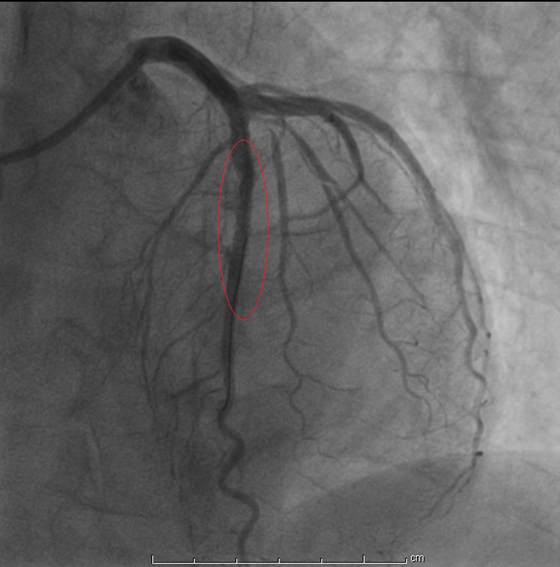

今年2月底,刘阿姨来到湘雅常德医院心内科,范爱德副主任医师仔细询问病史后,结合患者各种检查认为还是要考虑冠心病 心绞痛可能,建议刘阿姨住院,进一步完善冠脉造影明确冠心病。2月27日,据刘阿姨的冠脉造影显示,她的三条动脉都有不同程度的狭窄,其中一条动脉(左前降支)重度狭窄并钙化。心内科为刘阿姨做了冠脉介入治疗手术,于前降支近段及中段狭窄处植共植入2枚支架后,狭窄的血管顺利开通,心肌得到供血。历时近一年的求医之路,今天终于看到曙光,刘阿姨放心了……

支架植入术后